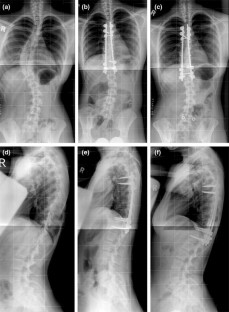

Fig. 1